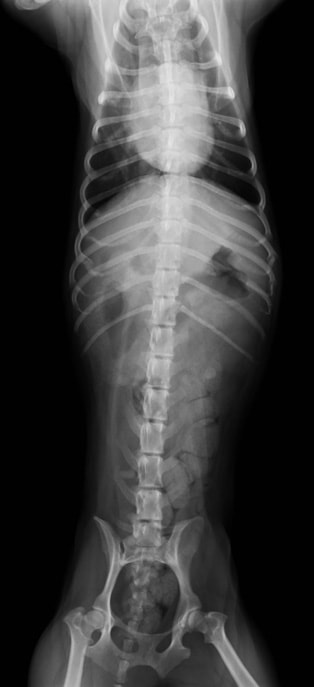

膀胱結石

膀胱結石 ( 症例-1 )

膀胱結石とは、膀胱内に結石が作られて、慢性的に頻尿、血尿、膀胱炎を起こします。

放っておけば、結石はどんどん大きくなり、膀胱や腎臓に負担がかかり、腎不全や、膀胱腫瘍に移行してしまう事があります。なるべく早めの外科的摘出をおすすめします。

![]() 【レントゲン写真】膀胱内に大きく白い結石が確認されます。 |